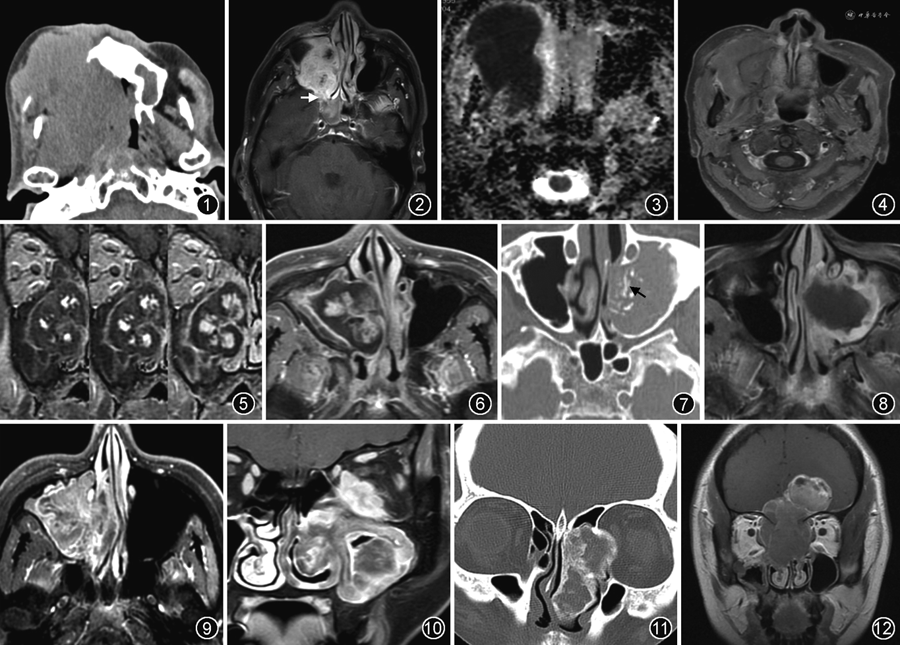

1.软组织肿块伴骨质破坏:可见于鳞癌、腺样囊性癌、恶性黑色素瘤、淋巴瘤等恶性肿瘤,出血坏死性鼻息肉和黏液囊肿等良性病变以及侵袭性真菌性鼻窦炎[3,5, 6, 7,10, 11,15]。(1)鳞癌为最常见的恶性肿瘤,表现为溶骨性骨质破坏、窦腔扩大,常通过骨质破坏区侵犯周围结构(图1),肿块的密度或信号不均匀,增强后不均匀强化,无特异性[2, 3,16]。(2)邻近的三叉神经分支增粗且强化,常提示为腺样囊性癌或鳞癌等,腺样囊性癌更常见[16](图2)。(3)腺样囊性癌常含有腺样结构和散在的微囊性结构,其ADC值与良性肿瘤相似,因此,在ADC图上肿块信号不低时,不能除外腺样囊性癌。(4)骨质破坏呈渗透性且骨质轮廓存在,典型表现呈“虚线状”骨质破坏,肿块与脑实质比较呈均匀等密度或等信号,DWI显示扩散受限,ADC值明显减低,增强后呈轻度或中度均匀强化,提示为淋巴瘤[2,10, 11,16](图3,4)。(5)肿块内可见片状或不规则T1WI高信号影、T2WI低信号影,可见于出血坏死性鼻息肉、侵袭性真菌性鼻窦炎、海绵状血管瘤、恶性黑色素瘤和伴出血的其他肿瘤[2,5,7,13, 14,16]。(6)动态增强扫描肿块呈“渐进性强化”(必须观察各时相图像才能准确判断),但增强后较长时间仍有部分区域未强化,提示为出血坏死性鼻息肉[7](图5,6)。(7)动态增强扫描肿块呈“渐进性强化”且最后能完全强化,提示为海绵状血管瘤[14]。(8)含色素较多的恶性黑色素瘤在鼻内镜下呈黑色或棕色肿块,T1WI呈高信号影、T2WI呈低信号影,增强后中度不均匀强化,诊断相对比较容易,但色素较少或无色素的恶性黑色素瘤表现不典型,常误诊为鳞癌等其他病变,只能依靠活检病理诊断[13]。(9)上颌窦腔扩大,窦壁呈吸收性骨质破坏导致骨壁缺损,病变可突入眼眶或颌面部,增强后肿块无强化而周边黏膜环形强化,提示为黏液囊肿[15]。

2.软组织肿块伴骨质破坏与增生硬化:常见于内翻性乳头状瘤、真菌球和侵袭性真菌性鼻窦炎,也可见于炎性肌纤维母细胞瘤等[5,12,17, 18, 19]。(1)CT显示肿块内点片状高密度影,MRI增强扫描呈环形或分隔样强化,提示为真菌球[17](图7,8);(2)CT显示骨质破坏伴骨质增生硬化,并常累及邻近的鼻窦外结构,MRI增强扫描呈环形或分隔样强化,没有明确强化的肿块,追问病史常有多年糖尿病或免疫低下疾病的病史,提示为侵袭性真菌性鼻窦炎[5]。(3)T2WI或增强扫描显示“脑回征”,提示为内翻性乳头状瘤[8,18,20](图9)。如果出现以下表现则提示内翻性乳头状瘤恶变:肿块局部“脑回征”消失、ADC值明显减低或动态增强扫描曲线类型呈平台型或流出型[4,8]。(4)肿块沿上颌窦壁环形分布呈“跑道征”,T2WI呈低或等信号,增强后明显强化并累及翼腭窝、颞下窝、眼眶或面颊部软组织等邻近结构,提示可能为炎性肌纤维母细胞瘤[19](图10)。(5)需要注意的是,鳞癌等恶性肿瘤可合并慢性鼻窦炎,也可伴有上颌窦壁骨质增生硬化。

2.嗅神经母细胞瘤:(1)肿块部位比较特殊,位于筛顶和鼻腔上部,常通过筛板或筛凹的骨质破坏区累及颅内,颅内肿块较大时呈典型的“哑铃状”表现,侵犯脑实质者肿块周边部出现囊变区[2,16,25](图12)。(2)嗅神经母细胞瘤改良Kadish分期:A期,肿瘤局限于鼻腔内;B期,肿瘤侵犯鼻窦;C期,肿瘤超出鼻腔或鼻窦范围;D期,肿瘤出现淋巴结转移或远处转移[26]。